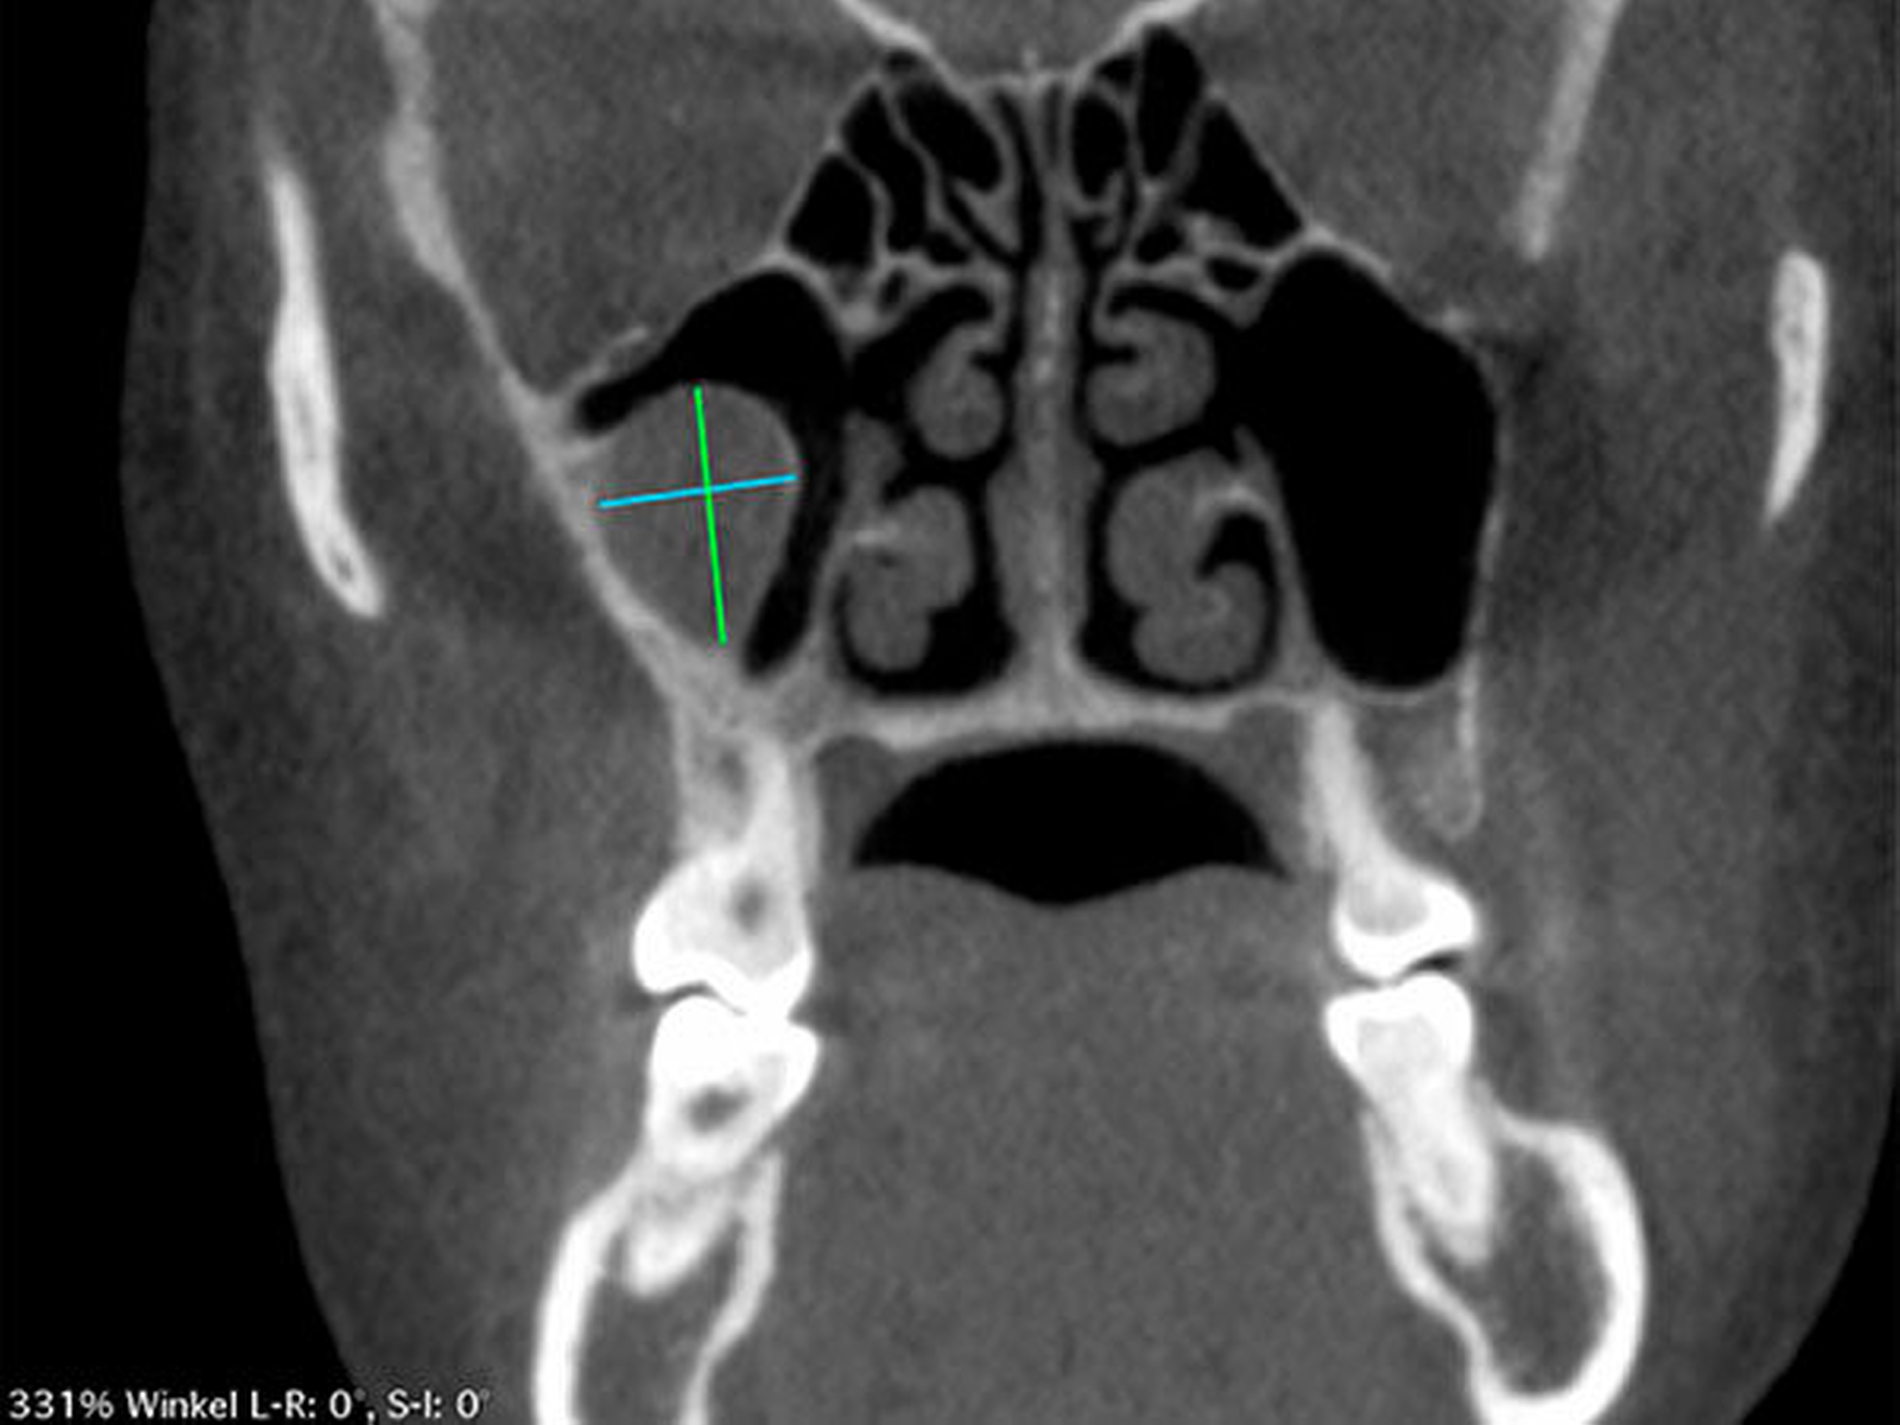

Die Durchführung einer digitalen Volumentomografie (DVT) zeigte die dreidimensionale Ausdehnung der eiförmigen Raumforderung mit einem Volumen von 2,34 cm3 (Abbildung 2).